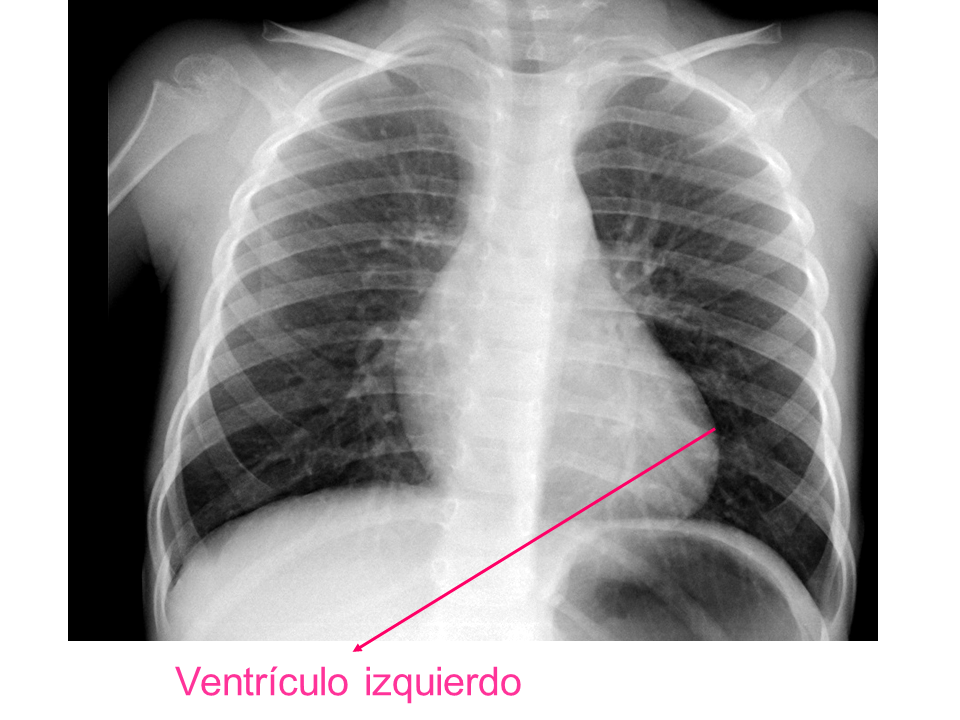

Para una adecuada lectura sistemática de la radiografía de tórax, debemos conocer la anatomía radiológica básica e identificar determinadas estructuras2.

• Ventrículo izquierdo